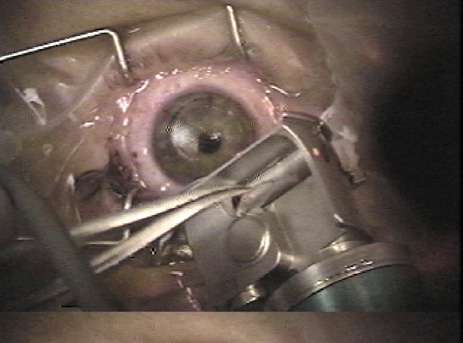

With a microkeratome, the suction ring usually is centered over the entrance pupil, but if using a suction ring that creates a flap of less than 9.5 mm in diameter some surgeons prefer to skew it toward the hinge to ensure that the hinge will not be located within the laser treatment zone. The ring is selected to create a diameter larger than the ablation zone; this is particularly important for hyperopic corrections and astigmatic corrections, as well as wavefront-guided treatments, all of which typically involve large areas of ablation, sometimes as much as a 10-mm diameter. Once the ring is properly positioned, suction is activated. The intraocular pressure should be raised to over 65 mm Hg and verified, preferably with a pneumotonometer (Fig. 4) rather than the less precise plastic Barraquer applanator, because low pressure can result in a poor quality, thin, or incomplete flap. Prior to making the lamellar cut, the surface of the cornea is moistened with proparacaine containing glycerin or with nonpreserved artificial tears. Balanced salt solution is avoided at this point because of the possibility of creating mineral deposits within the microkeratome that can interfere with its proper function. The microkeratome then is placed on the suction ring with the cornea moistened (Fig. 5) and its path is checked to assure that it is free of obstacles such as speculum, drape, or overhanging eyelid. The microkeratome then is activated, passing over the cornea (Fig. 6) until halted by the hinge-creating stopper, after which the microkeratome head is reversed off the cornea. Depending on the model, epithelial defects may be reduced by lowering the vacuum or discontinuing the suction during the reversal; other models require vacuum to remain at full pressure during reversal.

Fig. 4. The suction ring is placed, the vacuum activated, and the intraocular pressure is checked (a pneumotonometer is illustrated) to assure the IOP is above 65 mm Hg.